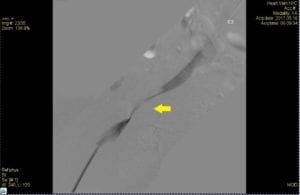

Authors: Tae An Choi ANP-BC, & Back Kim MD FACC. Heart Vein NYC, New York, New York Before (Right): 50 year-old male, a retail sales read more